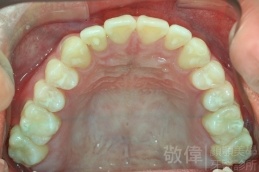

變臉矯正,原來戽斗妹跟大歪臉變成自信正妹

經由本院3D數影X光影像儀分析、與3D齒顎顏矯正技術,再配合口腔顎面正顎專科醫師施以正顎手術治療,雙方共同合作,使患者臉部外觀有很好的改善,大歪變小歪,產生了天南地北的大改變,她的人生也整個變得不一樣。

因為矯正與正顎手術的配合,使「戽斗妹」變成了「陽光正妹」,完全的改變了她的人生,在面對各種場合、與人交際都散發出自信微笑。所以,奉勸家長,如果小朋友有臉顎畸型的問題,應該考慮配合做這種簡單、安全、有效的正顎手術。

「3D齒顎顏矯正」,不止矯正您的牙齒,也會改變您的人生。「治療前」和「治療後」出社會的人生際遇一定會截然不同。